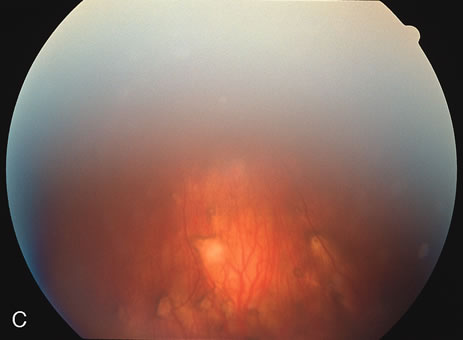

DIFFUSE SUBRETINAL FIBROSIS

Some patients present with subretinal bands that extend between chorioretinal scars. In addition there may be initial active yellow choroidal lesions that subsequently become atrophic. Vitreous cells are usually present although they may be few and difficult to detect. Visual acuity loss in these cases may be due to active choroidal neovascularization, subretinal bands under the fovea, or from cystoid macular edema. The vast majority of affected patients are women with a mean age of 27 years and both eyes are usually involved. The affected individuals tend to be myopic.49 The age range is from 6 years to 76 years and there is no racial predilection.40 Whether it is a separate disease or a more severe form of multifocal choroiditis is controversial (Figs. 10 and 11). Aggressive therapy is warranted because it has a poorer prognosis than most cases of multifocal choroiditis. This syndrome has been called either diffuse subretinal fibrosis or progressive subretinal fibrosis syndrome.

Fig. 10. A. Fundus photograph showing the subretinal fibrosis extending from the disc to the periphery in a case of diffuse subretinal fibrosis. B. Fundus photograph showing the marked fibrosis in the midperiphery. C. Multifocal choroiditis type lesions noted in the inferior retina.